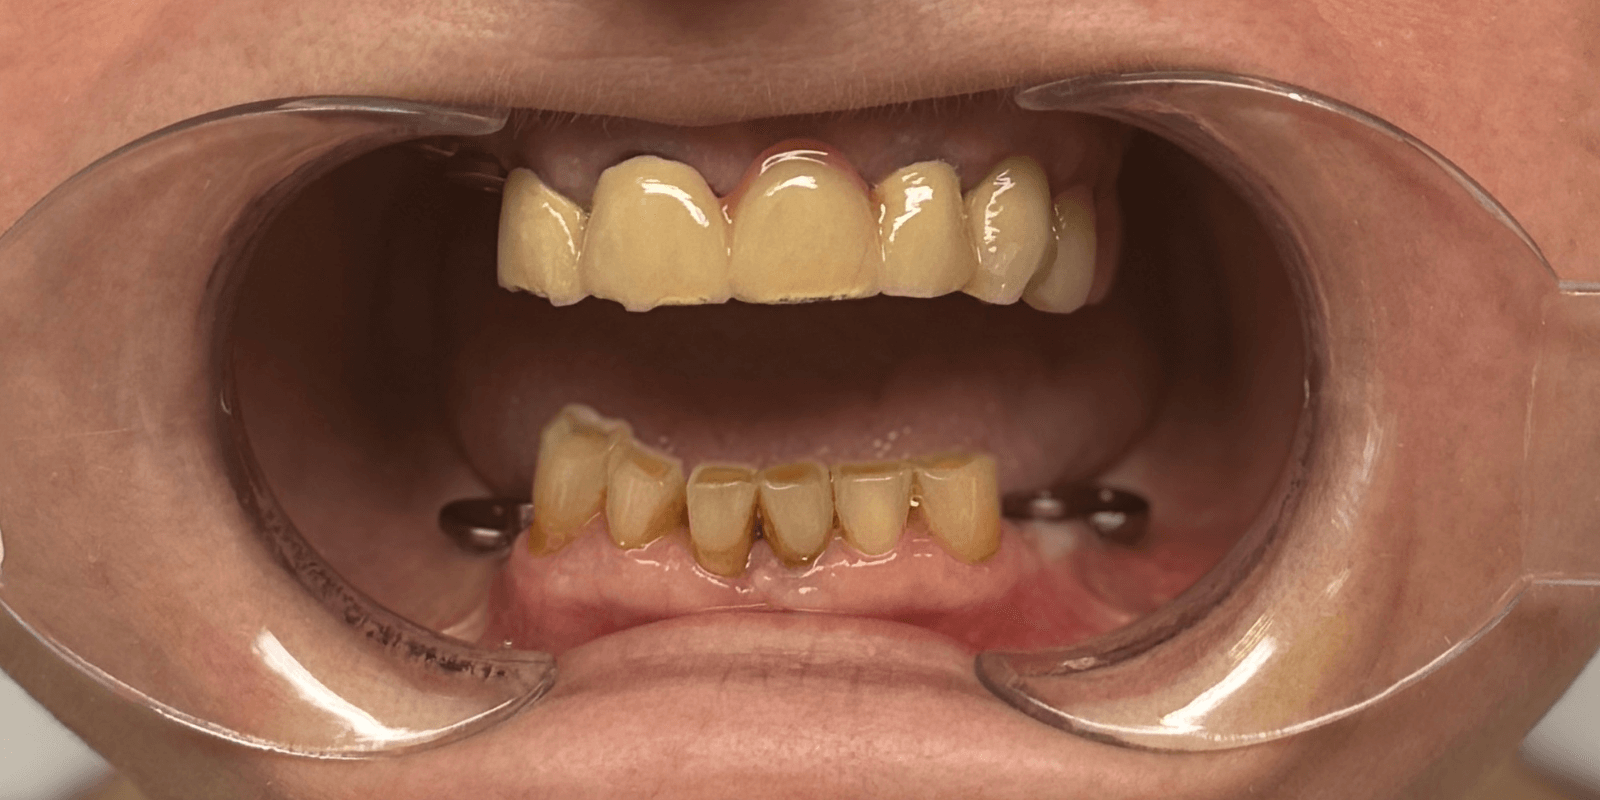

В нашу клинику обратилась пациентка с жалобами на эстетический дефект зубов, и невозможность пережевывать пищу. Врач провел предварительный осмотр и назначил КТ. На полученном КТ-снимке наблюдался металлокерамический мостовидный протез на верхней челюсти, керамическое покрытие на мостовидном протезе было повреждено (со сколами) в результате естественного износа из-за длительной эксплуатации.

В отдельных клинических ситуациях было бы уместно предложить съемное протезирование (бюгельный протез), однако в этом случае были показания к поднятию прикуса, поэтому пациентке был предложен следующий план лечения:

- Ортопедические конструкции изготовить из диоксида циркония, цвет bleach-2.